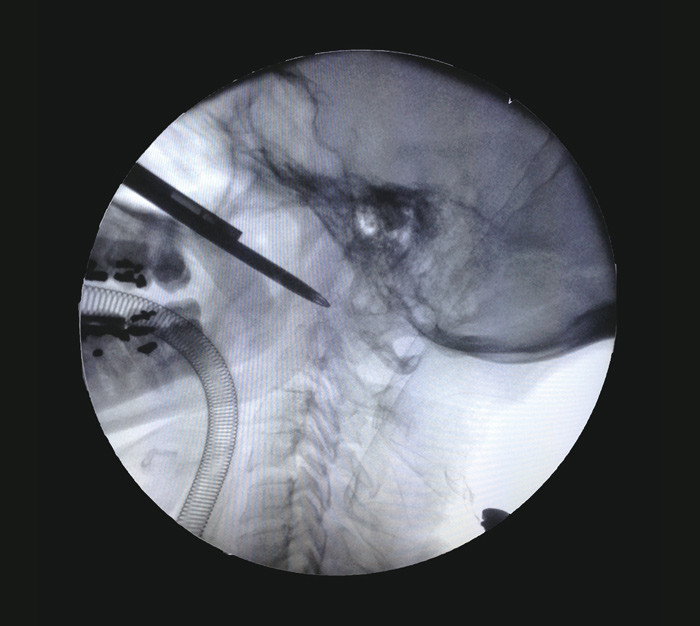

Åtte dager etter første innleggelse ble det i narkose høstet biopsimateriale og dyrkingsprøver fra prevertebralt område ved C1 – C2. Prøvetaking ble gjort via vertikal incisjon gjennom slimhinne og ligamentum longitudinale anterius. Inngrepet ble gjennomført transnasalt under endoskopisk veiledning (fig 2). Frysesnittundersøkelse og senere endelig histologi viste ikke tegn til malignitet, kun inflammatoriske forandringer med innslag av kalk eller beinrester (fig 3). Svar på dyrking fra prevertebralt område, i tre forskjellige prøver, viste penicillinresistente Staphylococcus aureus.